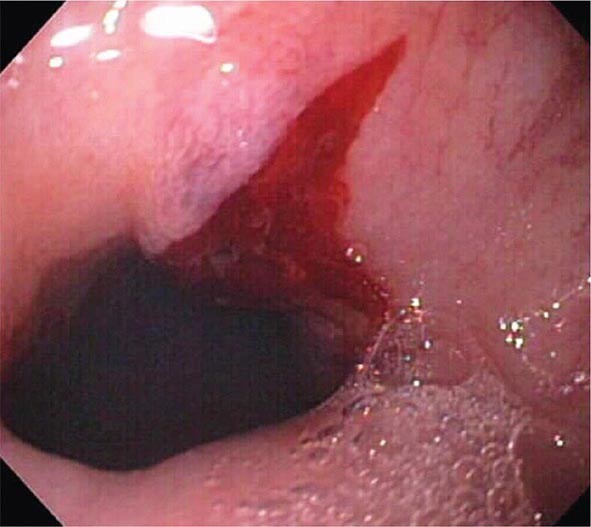

Mallory Weiss tear:

Longtitudinal tear in the mucous membrane, or inner lining, at the GEJ that can can cause significant bleeding and Painful Hematemesis. Associated w Boorhave syndrome.

Usually due to Alcohol or Bulemia